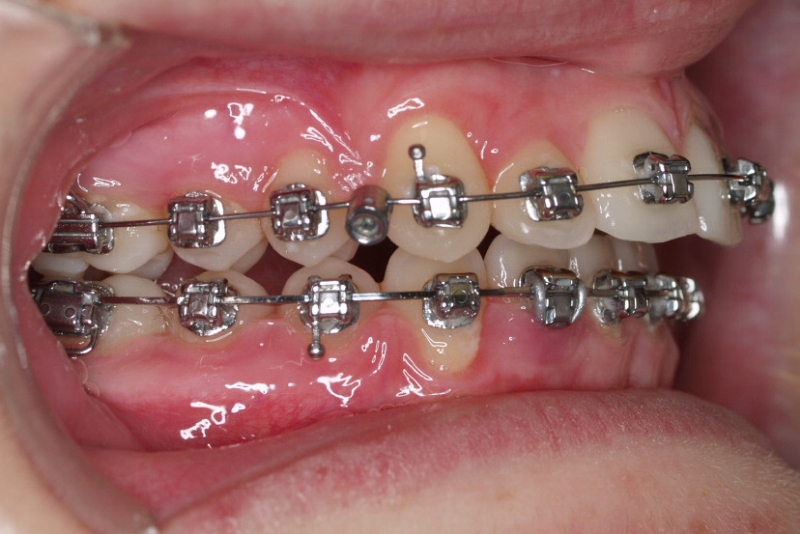

La paciente O.O. acude a nuestra consulta por:

– Canino 13 e incisivo lateral 42 en posición ectópica.

– Canino 23 incluido.

Con lo que decide realizarse un tratamiento de ortodoncia de duración de 24 meses con brackets damon Q.